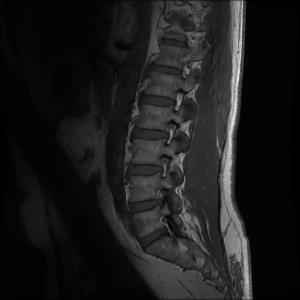

in een witte buis, mijn

rug eindigt in zwart-wit

klopgeesten bonken op de wand

voorspellen het beeld

ergens is het misgegaan

niet hier, maar daar

rug is kapot. het is voorbij,